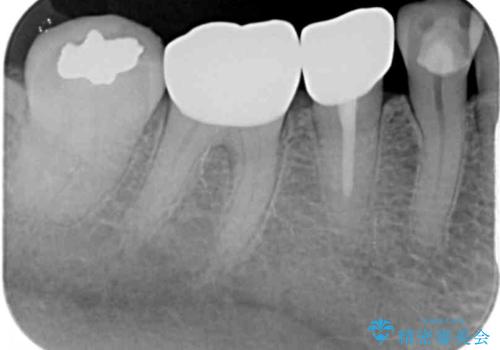

- セラミックが剥がれたり、歯質が欠けたりした奥歯を気にして来院された患者様です。

咬合力が強い方であったため、2歯をフルジルコニアクラウンにて補綴することとしました。

高強度のジルコニアクラウンとしたことで、強い咬合力でも壊れず、審美性を維持しやすい治療を行うことができました。